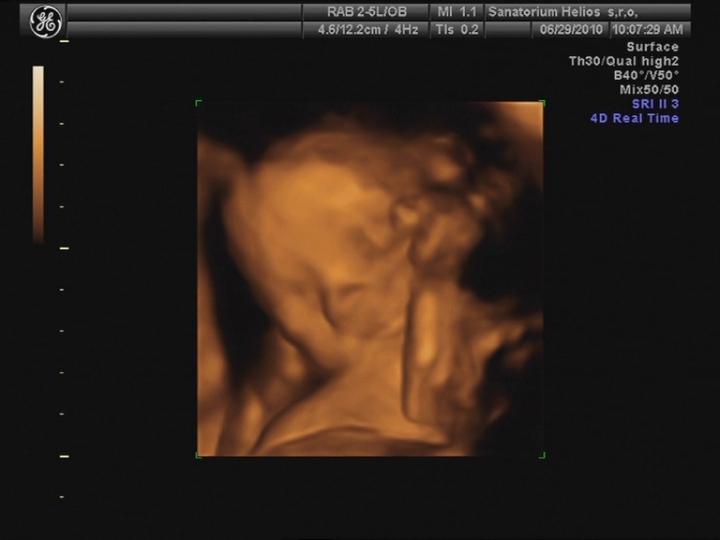

Už cítím pěkné kopanečky... 🙂)

25.5. jsme vstoupili do 5. měsíce .... nečekaně se to pohlo 🙂